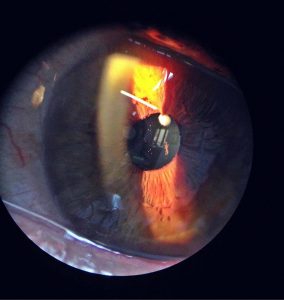

• 3er PREMIO: “SINEQUIA IRIS- CRISTALINO” presentado por Elena Sanz